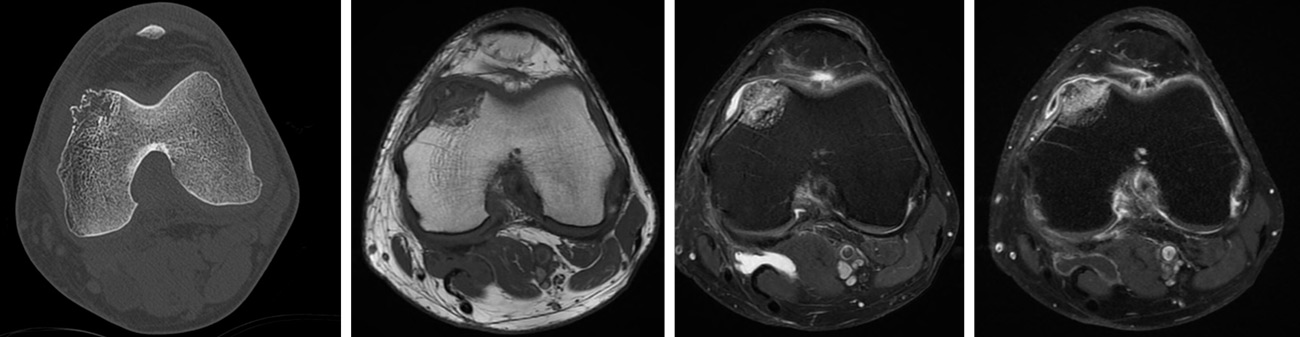

• CT-scan: Subchondral osteolytic lesion of the medial femoral condyle, with cortical breach.

• MRI: HypoT1, hyper T2, gado +

CT-scan: Subchondral osteolytic lesion of the medial femoral condyle, with cortical breach.